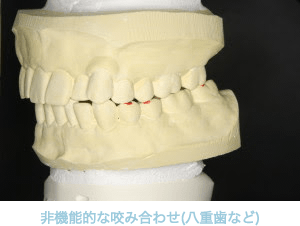

鏡の前で確認してみましょう。

下あごを前や横へずらした時に、奥歯が当たっている方は要注意です。

下顎を右側にずらした時、

犬歯のみ接触し奥歯には隙間ができ、

無理な力が加わらないため奥歯が長持ちします。

下顎を左側にずらした時奥歯が

全体的に当たってしまい強い横揺れが起こり、

歯が弱ってしまいます。